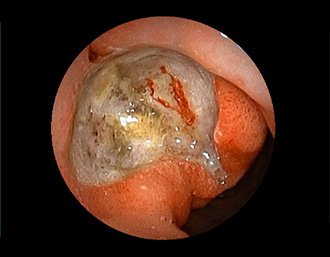

症例2:胃がん(66才男性)

術後胃(B-Ⅱope magen:十二指腸潰瘍手術)。吻合部の後壁側、軽度陥凹の白色病変を認める。生検:Group 5、Signent-ring cell carcinoma(印環細胞癌)と診断[早期胃癌]。高次医療機関へ紹介となり、残胃全摘術(リンパ節郭清)を行いました。